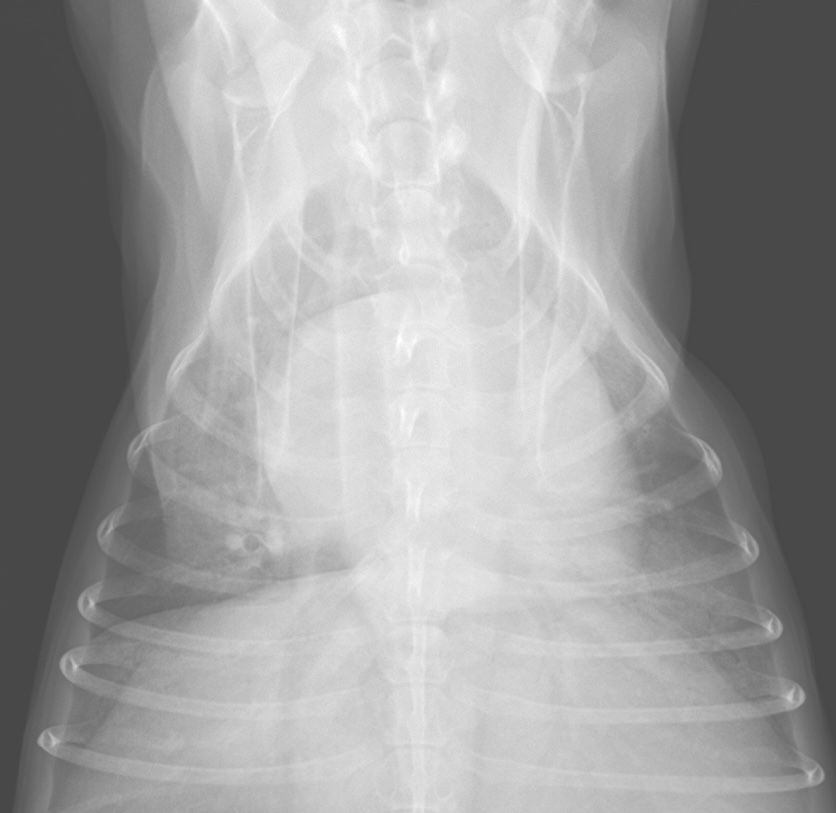

同一のわんちゃんのレントゲン画像

左:正常な肺の画像 右:肺水腫の肺の画像

側方向像も背腹方向像も特に後葉(肺の後ろの領域)が白くなっており、肺水腫の所見を認める